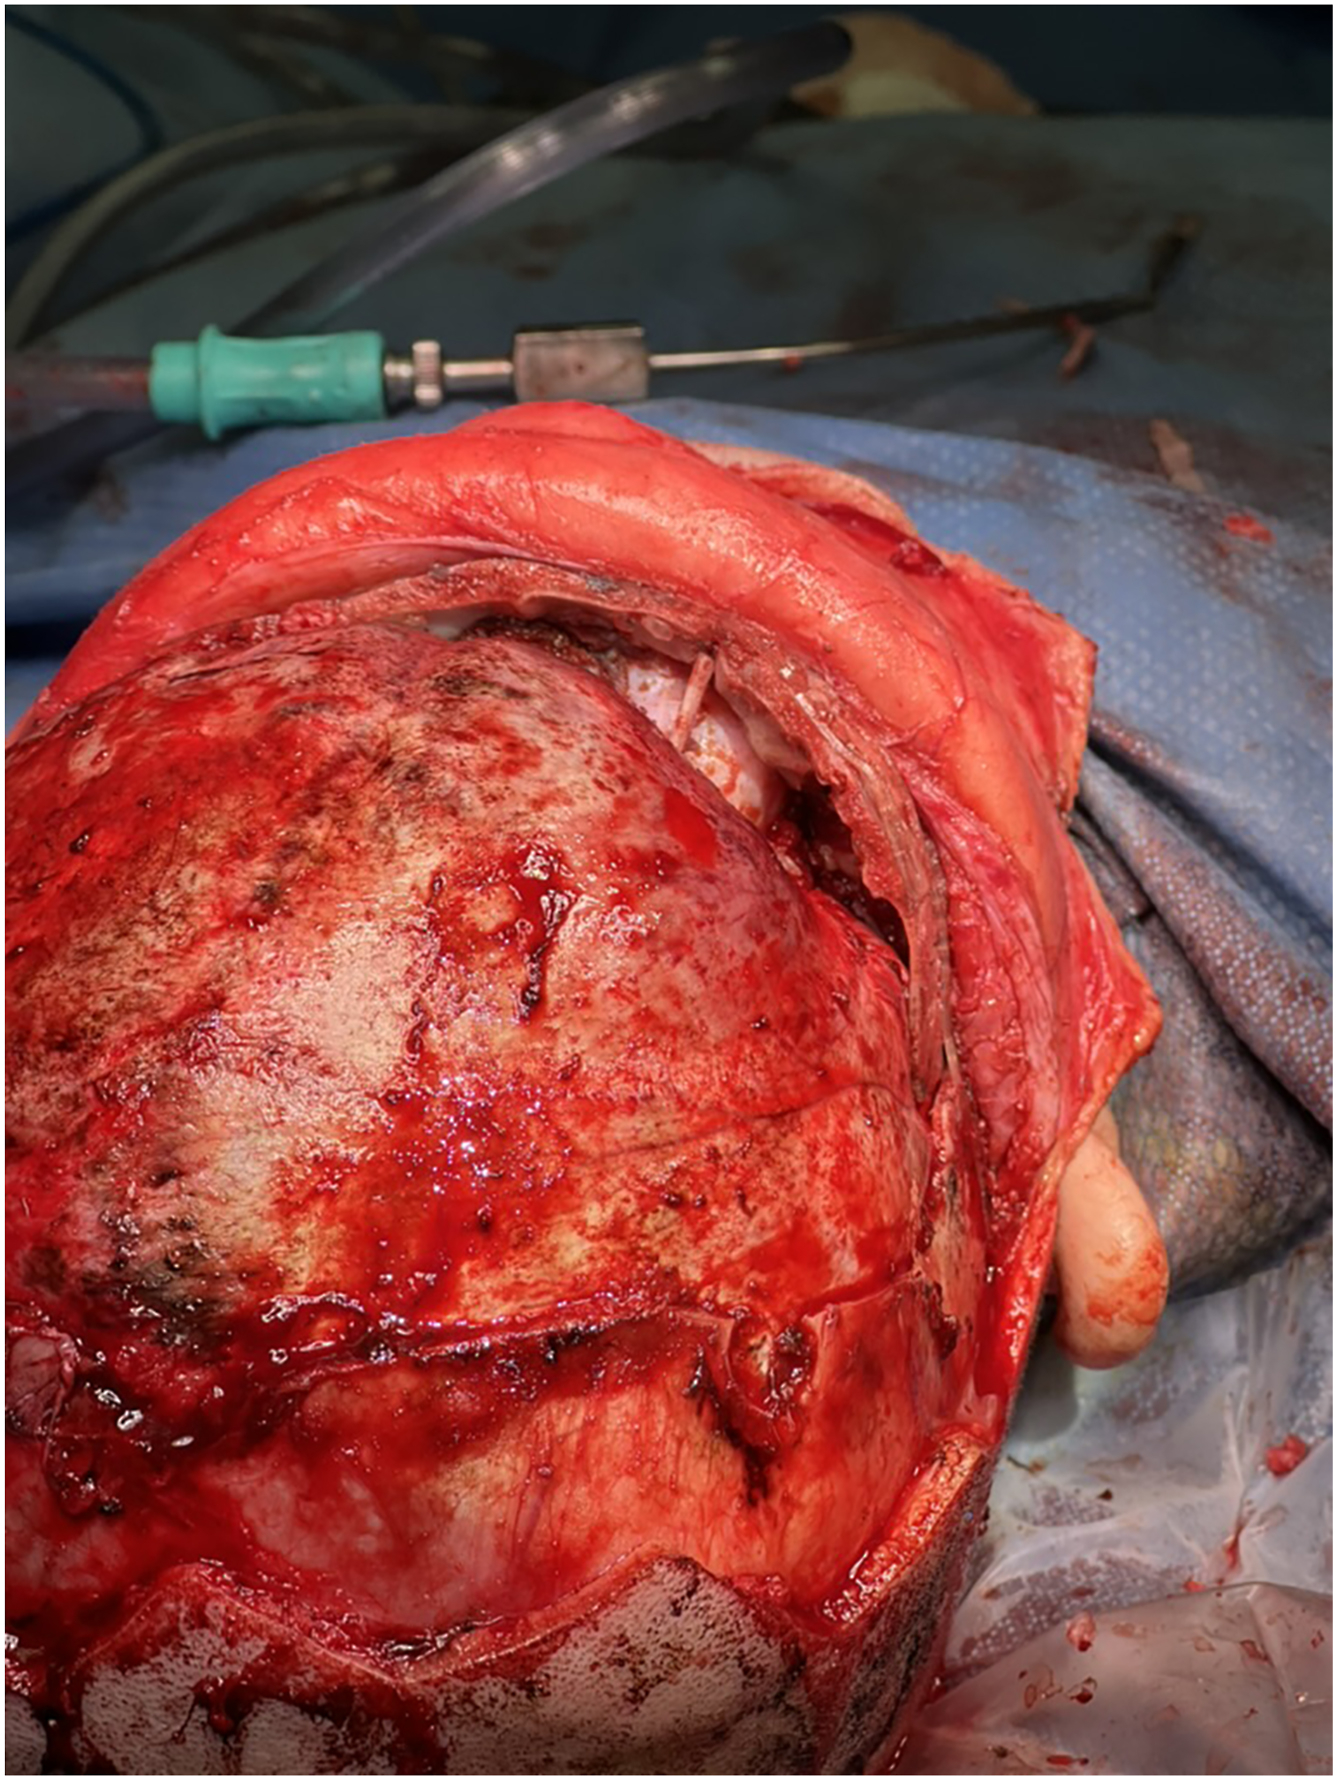

Open FOA has been the mainstay for cranial vault expansion and correcting the craniofacial deformities associated with coronal craniosynostosis. This technique involves a bicoronal incision with direct remodeling of the frontal bones and supraorbital bandeau such that the ipsilateral orbital rim is brought anterior and inferior to correct the Harlequin orbital deformity while the contralateral orbital rim is retruded. Depending on the phenotype and surgeon preference, surgery can also include ipsilateral superior orbital rim bone grafts to decrease the orbital height, contralateral interpositional orbital bone grafts to widen the contralateral orbit, and narrowing of the ipsilateral lateral orbital rim. Some surgeons perform bilateral bandeau advancement, whereas others advance primarily the affected side, hinging at the midline or at the contralateral orbit ( Fig. 3 ). This has also been performed using distraction osteogenesis following similar osteotomies on the ipsilateral fused suture, lateral calvarium, greater sphenoid wing, and orbital roof with a hinge osteotomy at the contralateral frontal bone. ,

Distraction osteogenesis has also been used in a minimally invasive approach, performing the same osteotomies and applying a cranial distraction device through 3 small incisions at the anterior fontanelle, ipsilateral pterion, and ipsilateral upper eyelid ( Fig. 4 ). Other minimally invasive approaches include endoscopic-assisted suturectomy followed by helmeting or spring-assisted surgery. One technical aspect of the procedure we believe critical particularly through minimal-incision approaches is adequate osteotomy and release of the advancing fronto-orbital complex from the sphenoid bone at the pterion; without release in this area, pterional retrusion persists postoperatively.